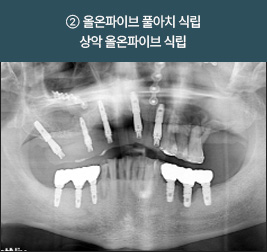

I      올온식스 풀아치 임플란트 사례      I

치료 기간 : 2021.05.08 ~ 2021.11.19

치료 기간 : 2022.05.17 ~ 2022.12.05